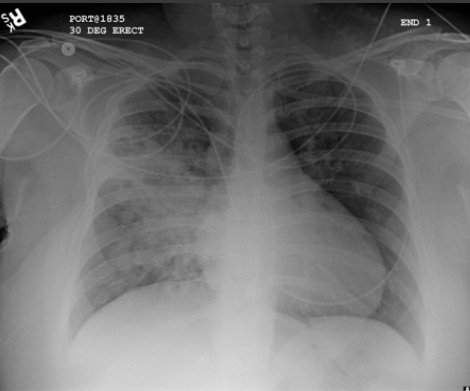

Considere una exploración por TC de tórax u otras pruebas diagnósticas mediante estudios por imágenes para detectar neumonía "complicada" o cambios atípicos en una radiografía de tórax, como cavitación, patrón de consolidación multifocal o derrame pleural.[89][Figure caption and citation for the preceding image starts]: Radiografía de tórax que muestra neumonía cavitante en el lóbulo superior izquierdoDe la colección del Dr. Jonathan Bennett. Usado con autorización [Citation ends].

[Figure caption and citation for the preceding image starts]: derrame pleural del lado izquierdoDe la colección del Dr. R Light. Usado con autorización [Citation ends].

[Figure caption and citation for the preceding image starts]: Opacificación aumentada de la región perihiliar derecha y del segmento superior de los lóbulos inferior y superior derechos coincidente con empeoramiento de neumonía por aspiraciónDe la colección del Dr. Roy Hammond. Usado con autorización [Citation ends].